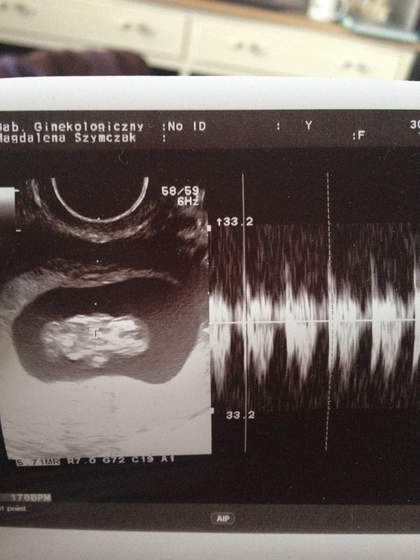

olcia i mysiak - gratuluje!!!!super fasolki w super mamach rosną:) wkleje też moją już jest troche bardziej zaawansowana:) widać człowieczka....ale może ja widzę:)

2012-05-31 20.10.15-1.jpg2012-05-31 20.10.26-1.jpg